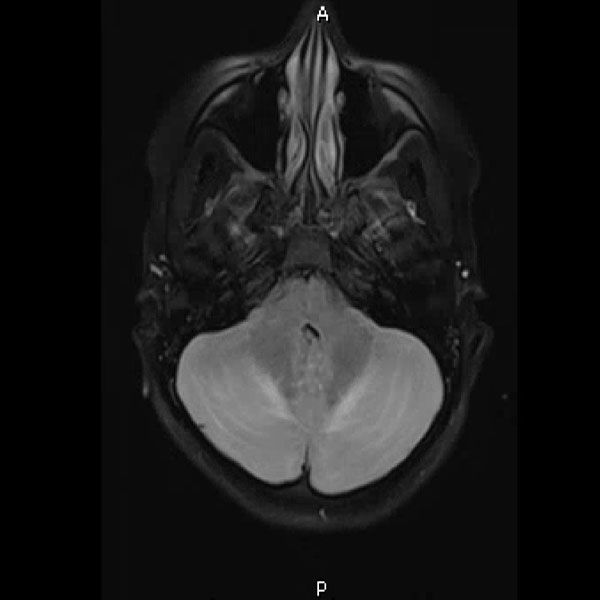

Urine toxicology, Tylenol level, Salicylate level, alcohol level thyroid studies, iron studies, hepatitis panel were normal. Urine pregnancy and COVID tests were negative. Head computed tomography (Head CT) showed mild hydrocephalus, and brain magnetic resonance imaging (MRI) showed increased signal folia and compression of the lower portion of the fourth ventricle and foramen of Magendie. She then had an emergency external ventricular drain placed (EVD) by pediatric neurosurgery, and the team started her on high-dose steroids and intravenous immunoglobulin (IVIG).

On the third day of admission, she developed new onset left-sided facial drooping, drooling, downbeat nystagmus, and difficulty following commands. An emergent subcortical craniectomy and decompression, duraplasty, and cerebellar biopsy were performed. A cerebellar biopsy was performed due to findings on brain MRI.

Consults were placed with pediatric neurology, pediatric infectious disease, pediatric hematology. Etiologies considered, included infectious, heavy metal poisoning, autoimmune, metabolic, and oncologic, with the following studies ordered: Cytomegalovirus Antibody(Ab) panel, and DNA, Coccidioides Ab, Epstein Barr Virus titers, fungal cerebrospinal fluid(CSF) panel, Human Immunodeficiency Virus testing, mycoplasma pneumoniae Ab, tuberculosis testing, toxoplasma Ab, meningitis panel, lactate dehydrogenase , uric acid, blood smear, CSF cytology, heavy metal panel, lead level, hemoglobin electrophoresis, complete blood count, complete metabolic panel, anti-nuclear Ab, N-Methyl-D-Aspartate receptor Ab, and ammonia. Lhermitte-Duclos disease versus cerebritis were also considered based on clinical status and radiological findings on brain MRI (Table 1).

Her biopsy result had nonspecific findings not consistent with Lhermitte-Duclos disease which is an extremely rare tumor of the cerebellum (dysplastic cerebellar gangliocytoma). The final diagnosis was lead encephalopathy.